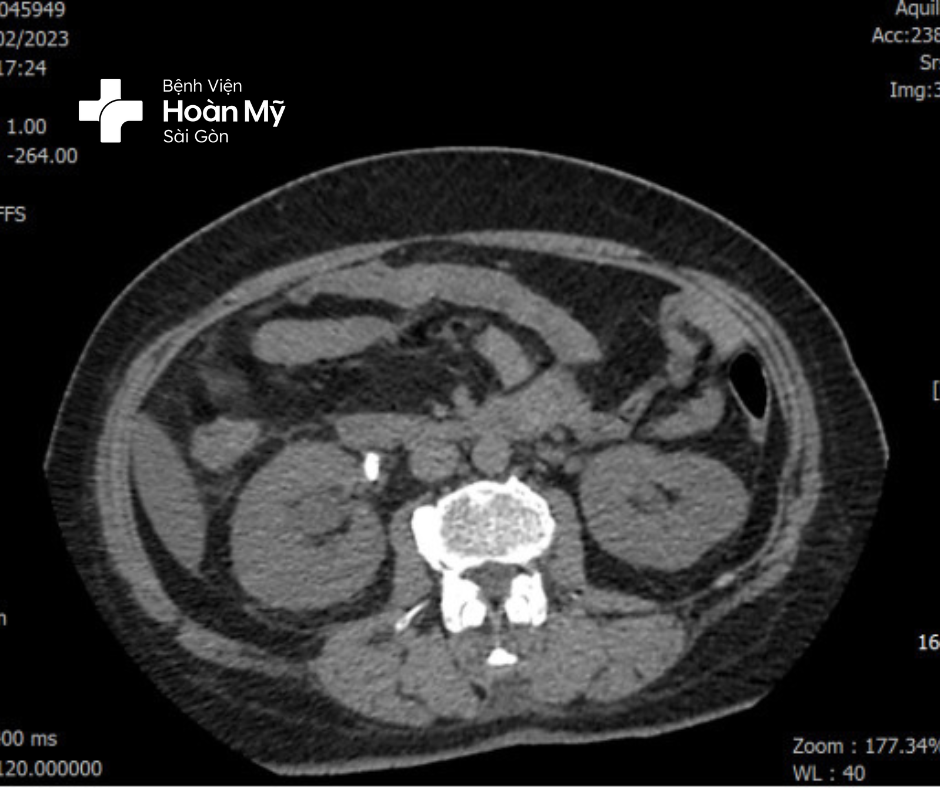

Hình 1: Sỏi niệu quản Phải, thận Phải ứ nước